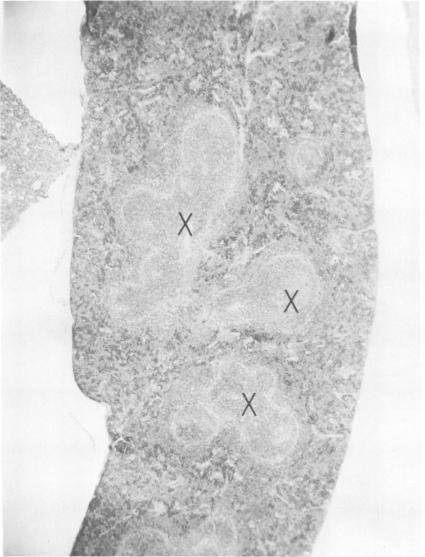

Intraperitoneal (i.p.) infection of BALB/c mice with 1,000 50% mouse lethal doses of the Karp strain of Rickettsia tsutsugamushi was inevitably lethal, and associated pathological alterations were confined to the peritoneal cavity. These included: (i) continuous proliferation of rickettsial organisms in peritoneal macrophages until death; (ii) hepatic granulomas appearing 6 days after infection and increasing in size and number until death; (iii) splenomegaly, resulting principally from proliferation of lymphoid tissue, and (iv) terminal peritonitis. Under two circumstances, i.p. infections with R. tsutsugamushi were not lethal: (i) infection with 100 50% mouse infectious doses of the Gilliam strain, which, in fact, resulted in immune protection against otherwise lethal Karp challenge; and (ii) Karp infection of animals immunized with the Gilliam strain. In both cases, the associated pathological abnormalities were, as with primary Karp infection, restricted to the peritoneal cavity. Also similar was the striking splenomegaly due to lymphoid proliferation, which was particularly prominent in immunized animals. In contrast to primary and lethal Karp infection, however, these infections were characterized by: (i) minimal and transient proliferation of rickettsial organisms in peritoneal macrophages; (ii) disappearance of hepatic granulomas; and (iii) absence of peritonitis. It was concluded that the survival of an animal bearing an i.p. infection of scrub typhus depended on its ability to concentrate a sufficiently vigorous immune response in the peritoneal cavity, resulting in the evolution of rickettsiacidal macrophages capable of suppressing the infection.

用1000个50%小鼠致死剂量的恙虫病东方体卡尔普株对BALB/c小鼠进行腹腔内(i.p.)感染必然致死,相关病理改变局限于腹腔。这些改变包括:(i)立克次体在腹腔巨噬细胞中持续增殖直至死亡;(ii)感染后6天出现肝肉芽肿,其大小和数量不断增加直至死亡;(iii)脾肿大,主要是由于淋巴组织增殖所致;以及(iv)终末期腹膜炎。在两种情况下,恙虫病东方体的腹腔内感染不会致死:(i)用100个50%小鼠感染剂量的吉列姆株进行感染,实际上这会产生针对原本致死的卡尔普株攻击的免疫保护;以及(ii)用吉列姆株免疫的动物感染卡尔普株。在这两种情况下,与原发性卡尔普感染一样,相关的病理异常都局限于腹腔。同样相似的是,由于淋巴组织增殖导致的显著脾肿大,在免疫动物中尤为突出。然而,与原发性和致死性卡尔普感染不同,这些感染的特征是:(i)腹腔巨噬细胞中立克次体的增殖极少且短暂;(ii)肝肉芽肿消失;以及(iii)无腹膜炎。得出的结论是,患有恙虫病腹腔内感染的动物的存活取决于其在腹腔内集中足够强烈的免疫反应的能力,从而导致能够抑制感染的杀立克次体巨噬细胞的进化。